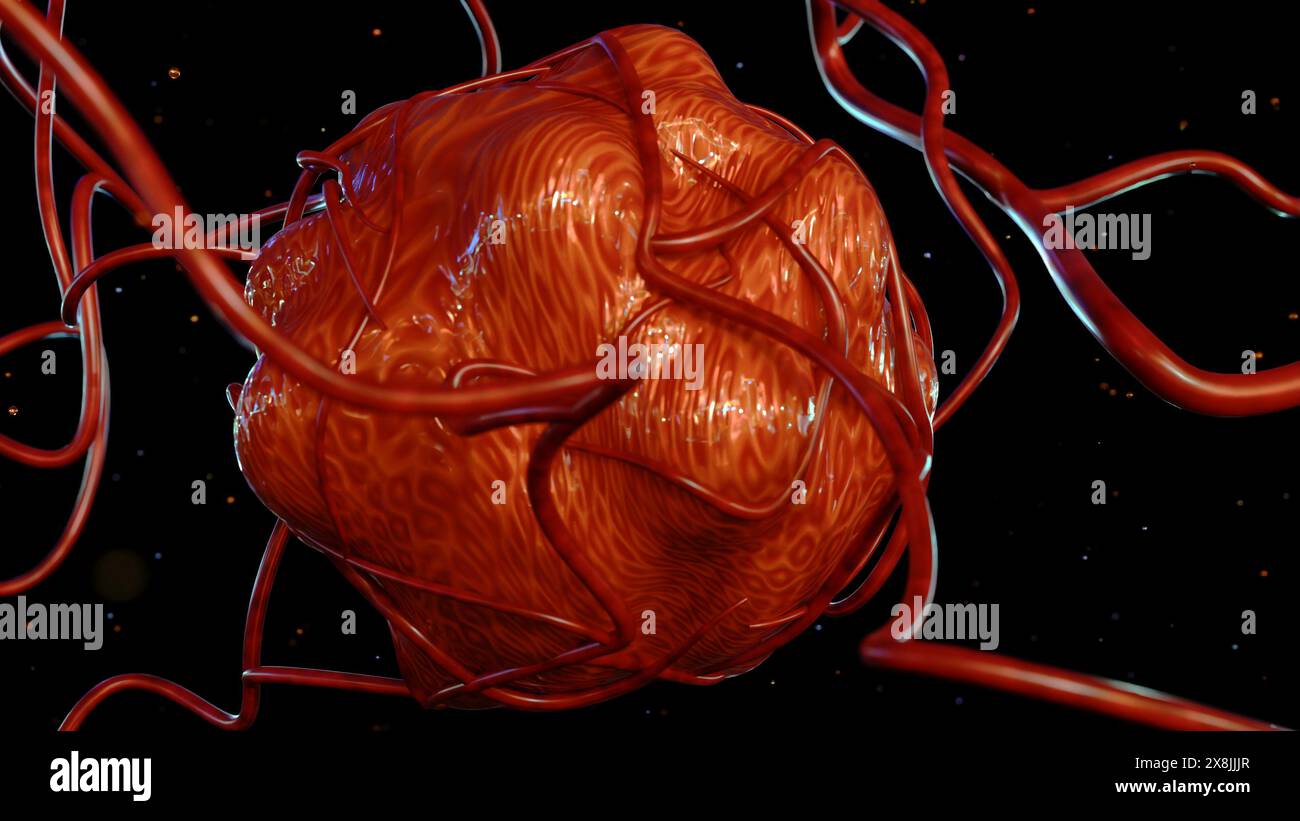

RF2X8JJJR–Die 3D-Darreichungsform von Krebs erfordert eine Blutversorgung, um die Nährstoffe und den Sauerstoff zu liefern, die sie zum Wachstum und Überleben benötigt

RF2X8JJJT–Die 3D-Darreichungsform von Krebs erfordert eine Blutversorgung, um die Nährstoffe und den Sauerstoff zu liefern, die sie zum Wachstum und Überleben benötigt

RF2X8JJJX–Die 3D-Darreichungsform von Krebs erfordert eine Blutversorgung, um die Nährstoffe und den Sauerstoff zu liefern, die sie zum Wachstum und Überleben benötigt